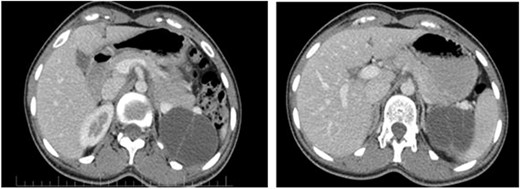

On ultrasound, the size, echogenicity, and parenchyma of the liver were normal, the bile ducts within and outside the liver were not dilated. Diameters of the port, bile ducts, and gallbladder were normal. The spleen and pancreas had normal size. And the pancreatic ducts were not dilated. A 61 × 50 mm cystic lesion with internal septa was observed adjacent to the upper bridge of the left kidney. The patient’s abdominal CT showed a clear thin-walled cystic lesion containing septa in the spleen with a size of 50 × 61 × 48 mm (Fig. 1).

The pancreatic cystic mass appearance on the patient’s CT scan.